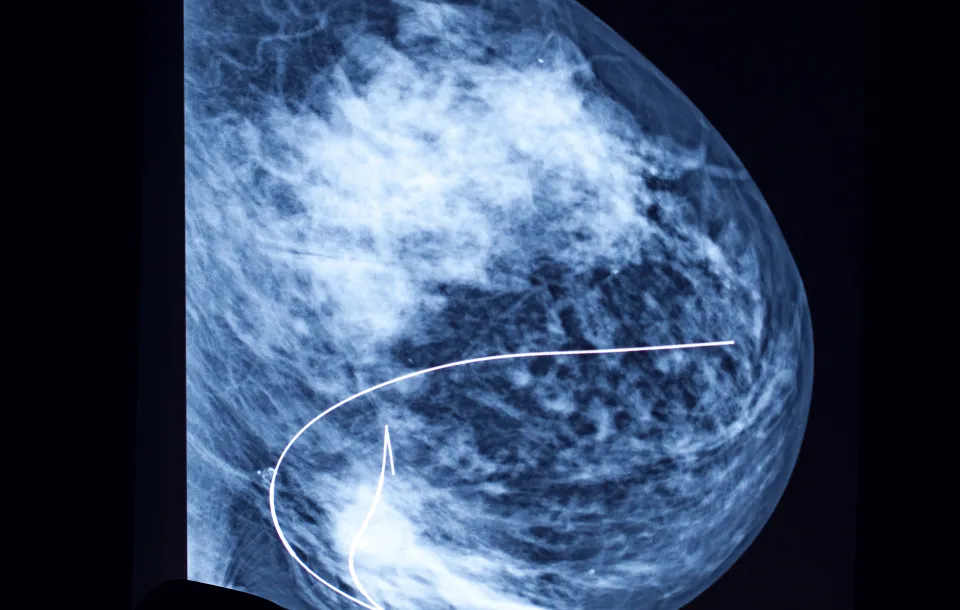

This webinar will explore the latest innovations in breast localization techniques and tools that enhance surgical precision and improve patient care. Breast localization can be achieved using various imaging modalities, which are especially useful for identifying non-palpable abnormalities. Participants will learn about new magnetic, radiofrequency, and color-guided seeds (currently in pre-FDA approval) that assist surgeons in accurately targeting areas of concern. This session will also examine the collaborative role of radiologists and technologists in these procedures and the exciting potential of these advancements to transform breast localization practices.

- Describe which imaging modalities, like ultrasound and MRI, are compatible with different localization tools

- Localizations utilizing Multiple Modalities

- Mammography 2D & 3D B. Ultrasound